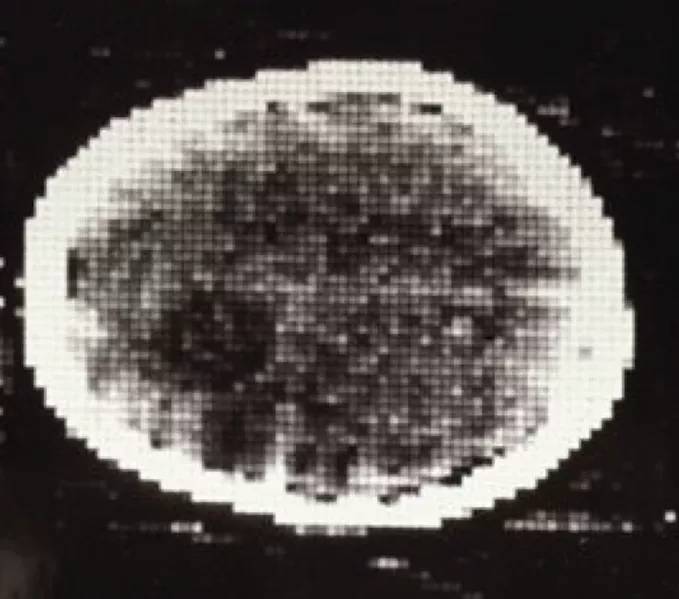

第一次臨牀CT掃描,可見腦瘤呈較深的斑點狀。‘Medical Imaging Systems: An Introductory Guide,’ Maier A, Steidl S, Christlein V, et al., editors., CC BY

就在那裏——在她的左額葉——一個李子大小的囊狀腫塊。於是,其他所有的大腦成像方法在此刻都過時了。